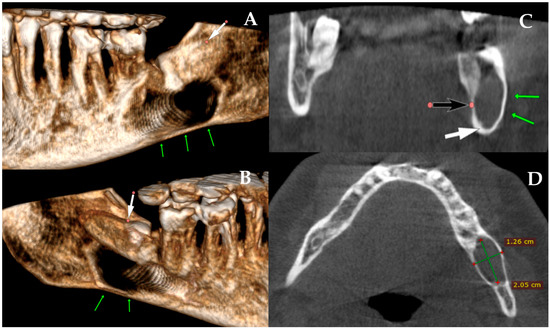

When CBCT Looks Borderline and Standard Radiology Is Inconclusive: Should We Plate or Should We Wait?

The main role of panoramic radiography lies in its rapid screening capability and its ability to detect and identify bone lesions, pathologies, and tooth-bearing structures. Since panoramic radiographs are widely used, they provide a good view of the jaw bones, maxillary sinus, and temporomandibular area. However, their major limitation is the reduced ability to accurately assess bone conditions, particularly in evaluating cortical integrity or identifying subtle, nondisplaced, or greenstick-type fracture lines. Other limitations include the presence of artifacts, image distortion, magnification variability, and high sensitivity to patient and film positioning, all of which can compromise image quality and diagnostic confidence. This 2D imaging method is still used worldwide, especially by dentists; however, this type of radiograph can be unpredictable due to structural superimposition and reduced ability to clearly establish, measure, and verify the precise dimensions, boundaries, and areas occupied by selected lesions. Many patients undergo panoramic imaging to assess possible mandibular fractures after trauma or following the removal of cysts, tumors, or impacted teeth. In most cases, the occurrence of a fracture without displacement can be misjudged, omitted, or underestimated. In such cases, either cone-beam computed tomography is performed or a detailed clinical examination before or during surgery, followed by intraoperative assessment, helps identify a possible fracture line, bone bending, mandibular instability, or the potential need for simultaneous prophylactic plating during dental procedures or the use of maxillomandibular fixation. This paper presents the author’s own experience regarding the limitations of panoramic radiographs in estimating bone condition and detecting fracture lines. Therefore, it is essential to highlight the role of prophylactic (preventive) mandibular plating (PMP) or fixation and to clarify when it should be considered. Full article

Figure 1